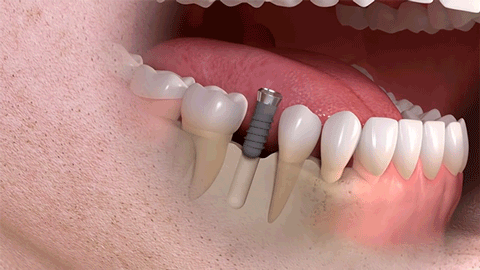

种植牙是医学界公认的理想修复方式,被誉为“人类的第三副牙”。相比活动假牙不舒服、难清洗、容易引起口腔黏膜病变,种植牙更稳固耐用,舒适美观,咀嚼功能好,一次种植,终生受用。种植牙不仅是中老年人的专利,年轻人因意外、牙病等造成牙齿缺失,也能够通过种植牙进行修复治疗,重获美丽笑容。